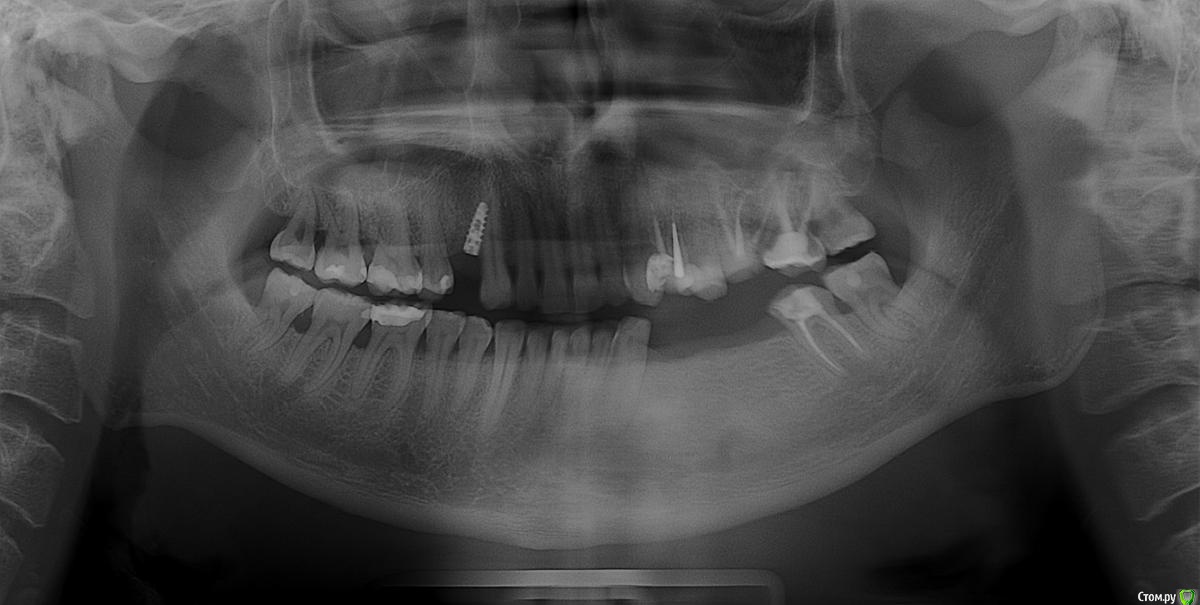

markanov Опубликовано 30 октября, 2015 Поделиться Опубликовано 30 октября, 2015 28.10.2015г. установили имплант.Врач говорит что всё будет нормально.Меня беспокоит клык, боль при надкусе и напряжение в зубе.Может его выкрутить? Меня отговаривают, говорят приживется.Проконсультируйте пожалуйста. Ссылка на комментарий

Larnary Опубликовано 30 октября, 2015 Поделиться Опубликовано 30 октября, 2015 (изменено) Выкручивать. Приживется-то он приживется,а вот дальше сплошные проблемы ждут. Слепок нормальный вряд ли получится снять,тк трансфер нормально не установить и путь введения для будущей коронки может быть не найден.проще говоря высока вероятность,что коронка не встанет. А если и встанет с цементной фиксацией,то абатмент будет весь спилен техником и коронка будет постоянно слетать. Про клык вам сказали. Есть вероятность повреждения корня и если вдруг,не дай Бог,его придется удалить в будущем,то на место клыка имплантат нормально уже не поставить,только под таким же неправильным углом.В общем,оставив этот имплантат на месте,вас может ожидать цепочка проблем в будущем Изменено 30 октября, 2015 пользователем Larnary 3 Ссылка на комментарий

diesel87 Опубликовано 30 октября, 2015 Поделиться Опубликовано 30 октября, 2015 Можно выкрутить и сразу переставить в верной ортопедической позиции. Ссылка на комментарий